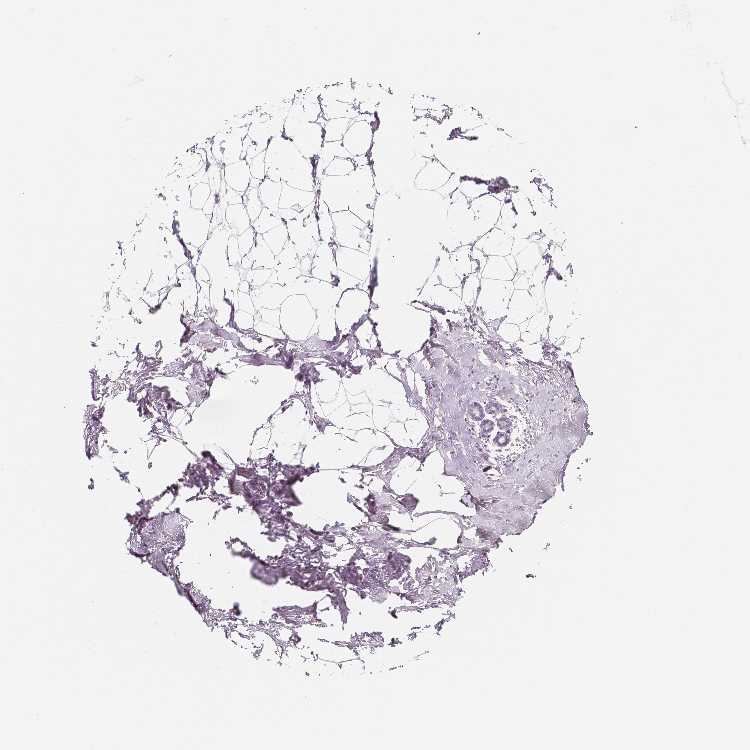

TISSUE PRIMARY DATA BREAST Show tissue menu

BREAST - Antibody stainingi

Antibody staining in the annotated cell types in the current human tissue is reported as not detected, low, medium, or high, based on conventional immunohistochemistry profiling in selected tissues. This score is based on the combination of the staining intensity and fraction of stained cells.

Each image is clickable and will lead to virtual microscopy that enables deeper exploration of all samples and also displays staining intensity scores, fraction scores and subcellular localization as well as patient and tissue information for each sample.

Antibody HPA013998Antibody HPA014144Antibody CAB068211

Adipocytes Not detectedNot detectedNot detected

Glandular cells Not detectedNot detectedNot detected

Myoepithelial cells Not detectedNot detectedNot detected